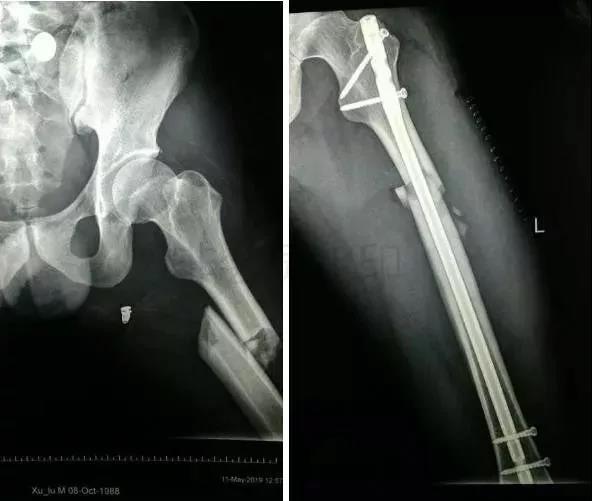

2)股骨干骨折

- 可以急诊做,也可以根据情况限期做。

- 多发伤,髓内钉,可能发生脂肪栓塞-肺栓。